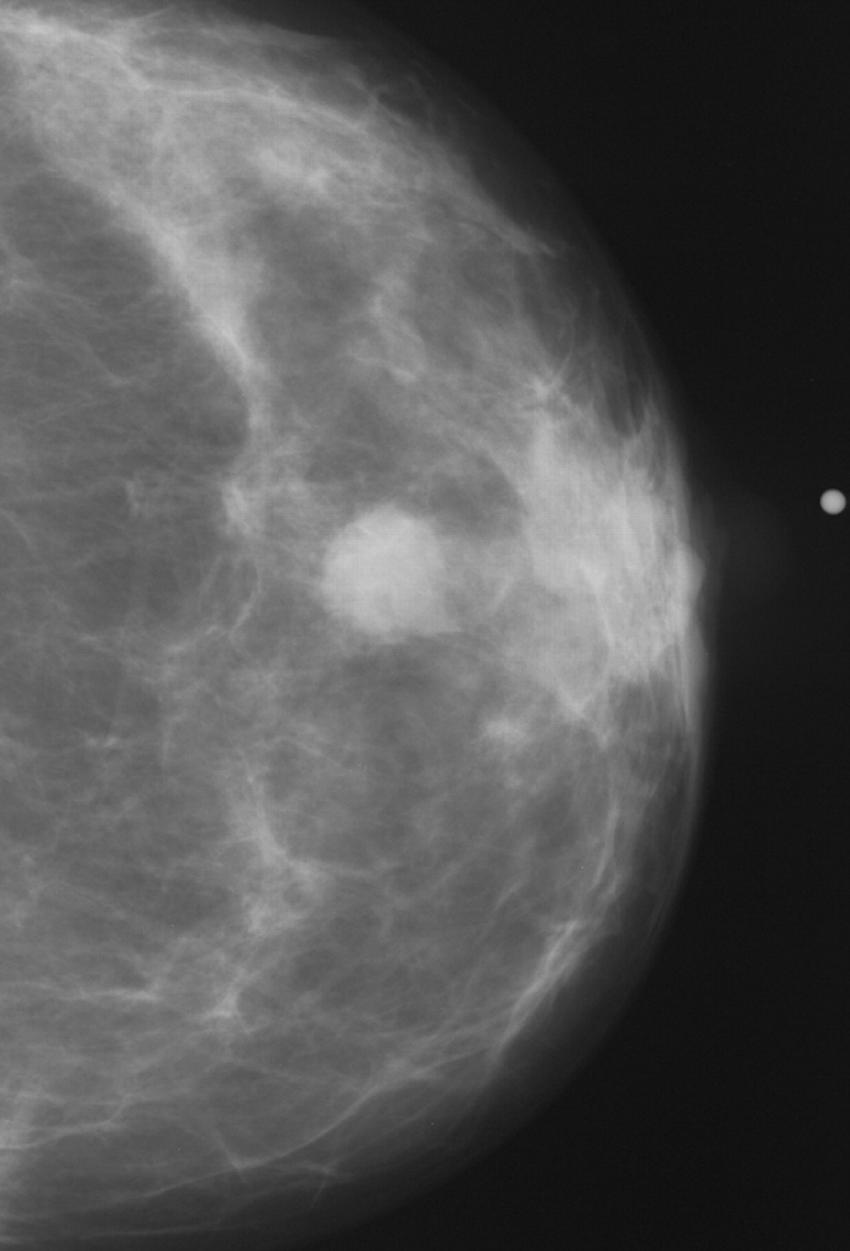

Figure 2. Normal mammogram.

Figure 1. Abnormal mammogram.